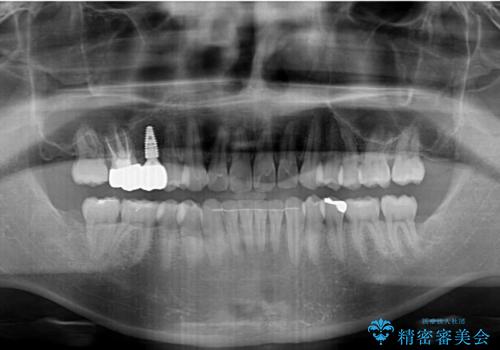

レントゲン撮影により、右上奥歯が折れていることが分かりました。

歯列不正は比較的軽微であったので、インビザラインによる矯正治療とし、矯正治療中にタイミングを見て抜歯とインプラント埋入を行う予定としました。